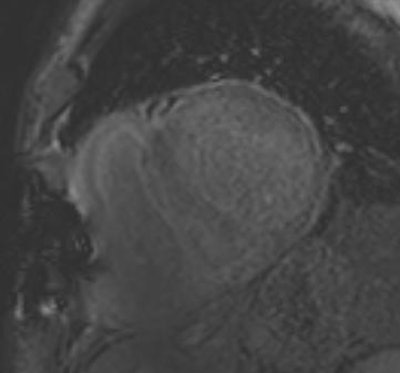

A 78-year-old man with cardiac amyloidosis: Nulling of "normal" myocardium is impossible, typical for storage disease. A PET/CT scan confirmed the diagnosis.The demand for CMR exams increased a lot during my first year of using CMR, and our team is already in need of reinforcement. In the future, we will probably have to handle more and more patients and we are therefore expanding our staff and starting to train more colleagues.